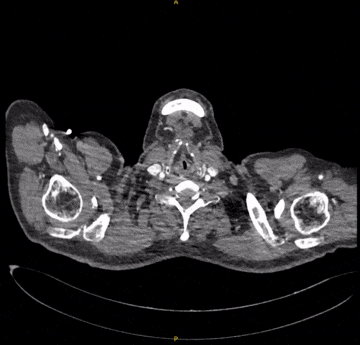

患者男,73岁,因“发现腹主动脉瘤3年余”入院。既往高血压、糖尿病史,长期吸烟。术前CTA显示肾下腹主动脉瘤,近端瘤颈充足,左侧髂内动脉狭窄,右侧正常。

手术采用腹主分支支架,主体释放后行交叉腿髂支延伸。

造影示肾下腹主动脉瘤

选用28-14-140mm主动脉覆膜支架